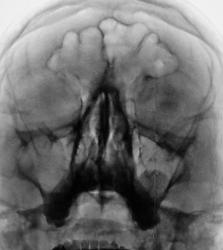

Пол пациента: Мужской пол Тип патологии: Другое Область исследования: Челюстно-лицевая область и шея Методы исследования: Rg Поступает в высшую школу милиции. Направлен на рентгенографию ППН. https://radiomed.ru/sites/default/files/styles/case_slider_image/public/user/12/2.dscn1174a.jpg?itok=_hRRR14D ID:26746 Втр, 05/03/2013 - 18:44 #1 Глазков Игорь А... Не на сайте Был на сайте: 11 месяцев 2 недели назад Зарегистрирован: 19.12.2008 - 20:41 Публикации: 1597 Очень похоже на кистозное образование левой верхне-челюстной пазухи. Прийди к Себе Втр, 05/03/2013 - 19:03 #2 Сергей Кузьминов Не на сайте Был на сайте: 1 год 2 месяцев назад Зарегистрирован: 06.10.2012 - 15:51 Публикации: 11813 Да,киста левой верхнечелюстной пазухи. Втр, 05/03/2013 - 23:15 #3 Наталия Васильевна Не на сайте Был на сайте: 5 лет 11 месяцев назад Зарегистрирован: 25.09.2011 - 09:02 Публикации: 754 Киста-кистой, а что за дырочка в лобной пазухе слева? Наложение теней грануляций? Ср, 06/03/2013 - 11:10 #4 Гаврилов Кирилл... Не на сайте Был на сайте: 8 лет 2 недели назад Зарегистрирован: 03.11.2009 - 21:50 Публикации: 87 Киста левой верхнечелюсной пазухи. Как вариант - локальное истончение стенки левой лобной пазухи (ИМХО) Рентгеновы лучи никогда не ошибаются. Ошибаемся мы, переводя их на свой язык Ср, 06/03/2013 - 19:14 #5 maker4ik Не на сайте Был на сайте: 8 лет 9 месяцев назад Зарегистрирован: 19.10.2011 - 17:49 Публикации: 2682 С такой кистой он еще долго поступать будет. Пнд, 11/03/2013 - 00:33 #6 brainmodel Не на сайте Был на сайте: 4 месяцев 3 недели назад Зарегистрирован: 18.03.2010 - 22:04 Публикации: 2881 Наталия Васильевна wrote: Киста-кистой, а что за дырочка в лобной пазухе слева? .. Бандыцкая пуля пролетела! Скиалогия нормы в лобных. Кистовидная тень в альвеолярной бухте левой гайморовой пазухи. Verum plus uno esse non potest. Пнд, 11/03/2013 - 20:04 #7 Наталия Васильевна Не на сайте Был на сайте: 5 лет 11 месяцев назад Зарегистрирован: 25.09.2011 - 09:02 Публикации: 754 brainmodel wrote: Бандыцкая пуля пролетела! Скиалогия нормы в лобных. Кистовидная тень в альвеолярной бухте левой гайморовой пазухи. [/quote] Ну, вот-еще не поступил, а уже пули свистят! А кисту можно и прооперировать, и пули не страшны, ему же в противогазе бегать не надо.

Очень похоже на кистозное образование левой верхне-челюстной пазухи.

Да,киста левой верхнечелюстной пазухи.

Киста-кистой, а что за дырочка в лобной пазухе слева? Наложение теней грануляций?

Киста левой верхнечелюсной пазухи. Как вариант - локальное истончение стенки левой лобной пазухи (ИМХО)